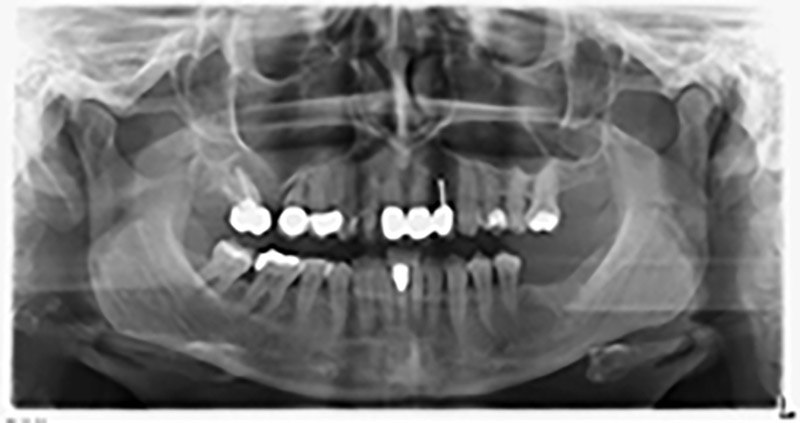

Die 59-jährige Patientin wurde mit einer fortgeschrittenen Parodontitis vorstellig, beschrieb ein ungutes Gefühl und einen schlechten Geschmack ausgehend vom ersten Quadranten distal. Die klinische Untersuchung zeigte allgemein erhöhte Taschentiefen und einen stark fortgeschrittenen Knochenabbau in regio 16 und 14. Die radiologische Untersuchung untermauerte den Befund (Abb. 1). Die Zähne 16 und 14 waren nicht zu erhalten.

Abb.1: Orthopantomogramm mit Knochenabbau in Regio 16–14.*